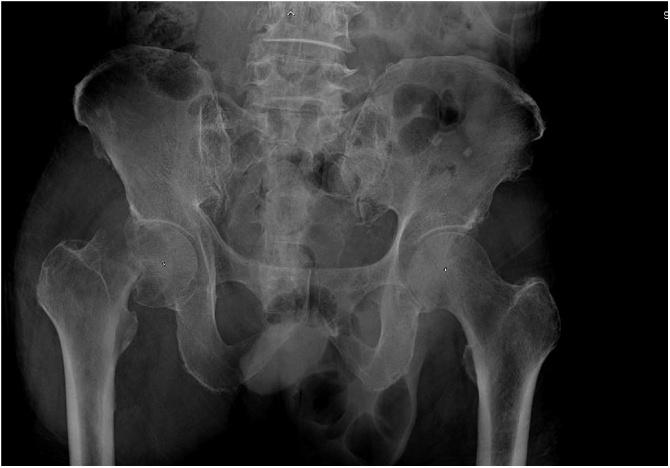

A 75-year-old male had right hip pain for two weeks after falling on his right hip. The patient was diagnosed as pathological fracture with hematologic malignancy. He was scheduled for bipolar hemiarthroplasty. However, an intraoperative finding found that the hip joint was filled with pus. The treatment was successful with a two-stage procedure. The first stage was implantation of an antibiotic cement spacer and the second stage was total hip replacement.

一名75岁男性在右髋部摔倒后右髋部疼痛两周。该患者被诊断为血液系统恶性肿瘤导致的病理性骨折。他计划接受双极半髋关节置换术。然而,术中发现髋关节充满脓液。通过两阶段手术治疗成功。第一阶段是植入抗生素骨水泥间隔物,第二阶段是全髋关节置换。